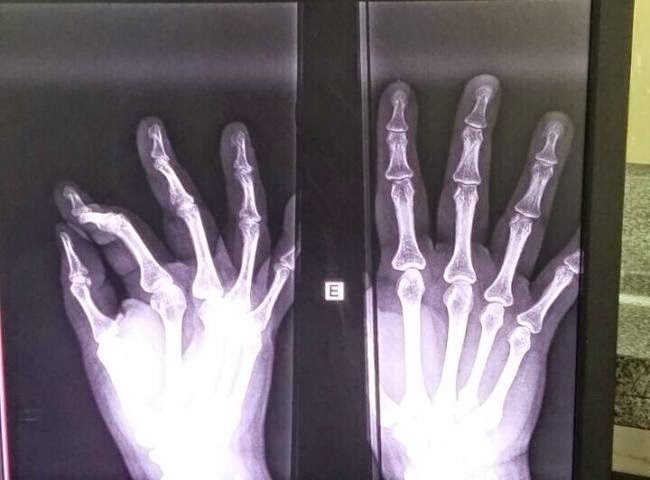

Uma t�cnica de enfermagem foi agredida e teve o dedo indicador direito quebrado, na noite desta quinta-feira (16/4), na UPA (Unidade de Pronto Atendimento), Coronel Antonino em Campo Grande. De acordo com testemunhas que preferiram n�o se identificar, a autora � uma gestante que aguardava por atendimento m�dico no local de repouso da Unidade.

No local, que � de triagem infantil, a mulher jogou um capacete e uma bolsa contra os funcion�rios. N�o contente, a autora ent�o jogou uma garrafa de �gua contra a porta. Posteriormente ela chutou a mesma porta, na qual a funcion�ria estava com a m�o para fech�-la, momento em que teve o dedo quebrado.